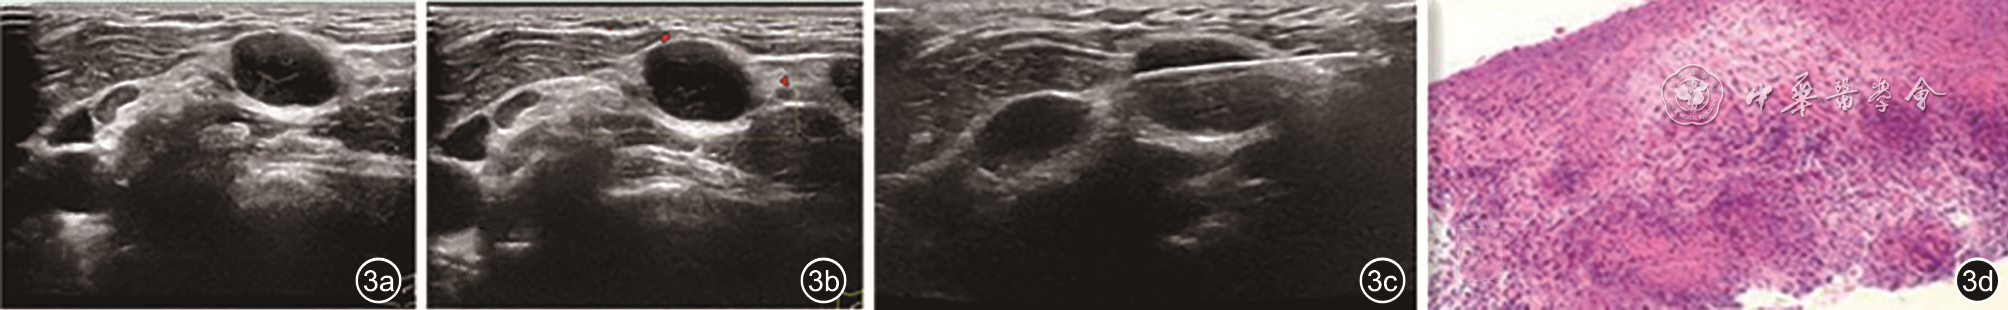

图3 结核感染颈部淋巴结受累常规超声、超声引导下粗针穿刺活检及病理图像。图a为二维超声图像;图b为能量多普勒超声图像;图c为超声引导下粗针穿刺活检图像;图d为常规病理图像(HE ×40),常规病理结合免疫组化证实为慢性肉芽肿性炎症伴坏死及多核巨细胞反应,考虑结核